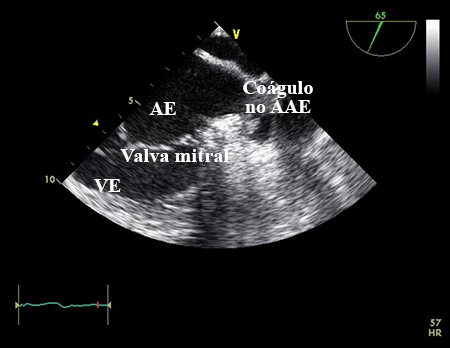

ecocardiografia transesofágica (ETE)

Discuta com um cardiologista sobre a possibilidade de realizar uma ETE, se disponível, em pessoas com fibrilação atrial quando:[1][3]

A ETT demonstrar alguma anormalidade (como valvopatia cardíaca) que justifique uma avaliação mais específica

A ETT for tecnicamente difícil e/ou de qualidade questionável e houver necessidade de descartar anormalidades cardíacas

Estiver considerando a cardioversão guiada por ETE.

[Figure caption and citation for the preceding image starts]: Ecocardiografia transesofágica mostrando coágulo no apêndice atrial esquerdo. AE, átrio esquerdo; AAE, apêndice atrial esquerdo; VE, ventrículo esquerdoDo acervo de Dr. Bharat Kantharia [Citation ends].